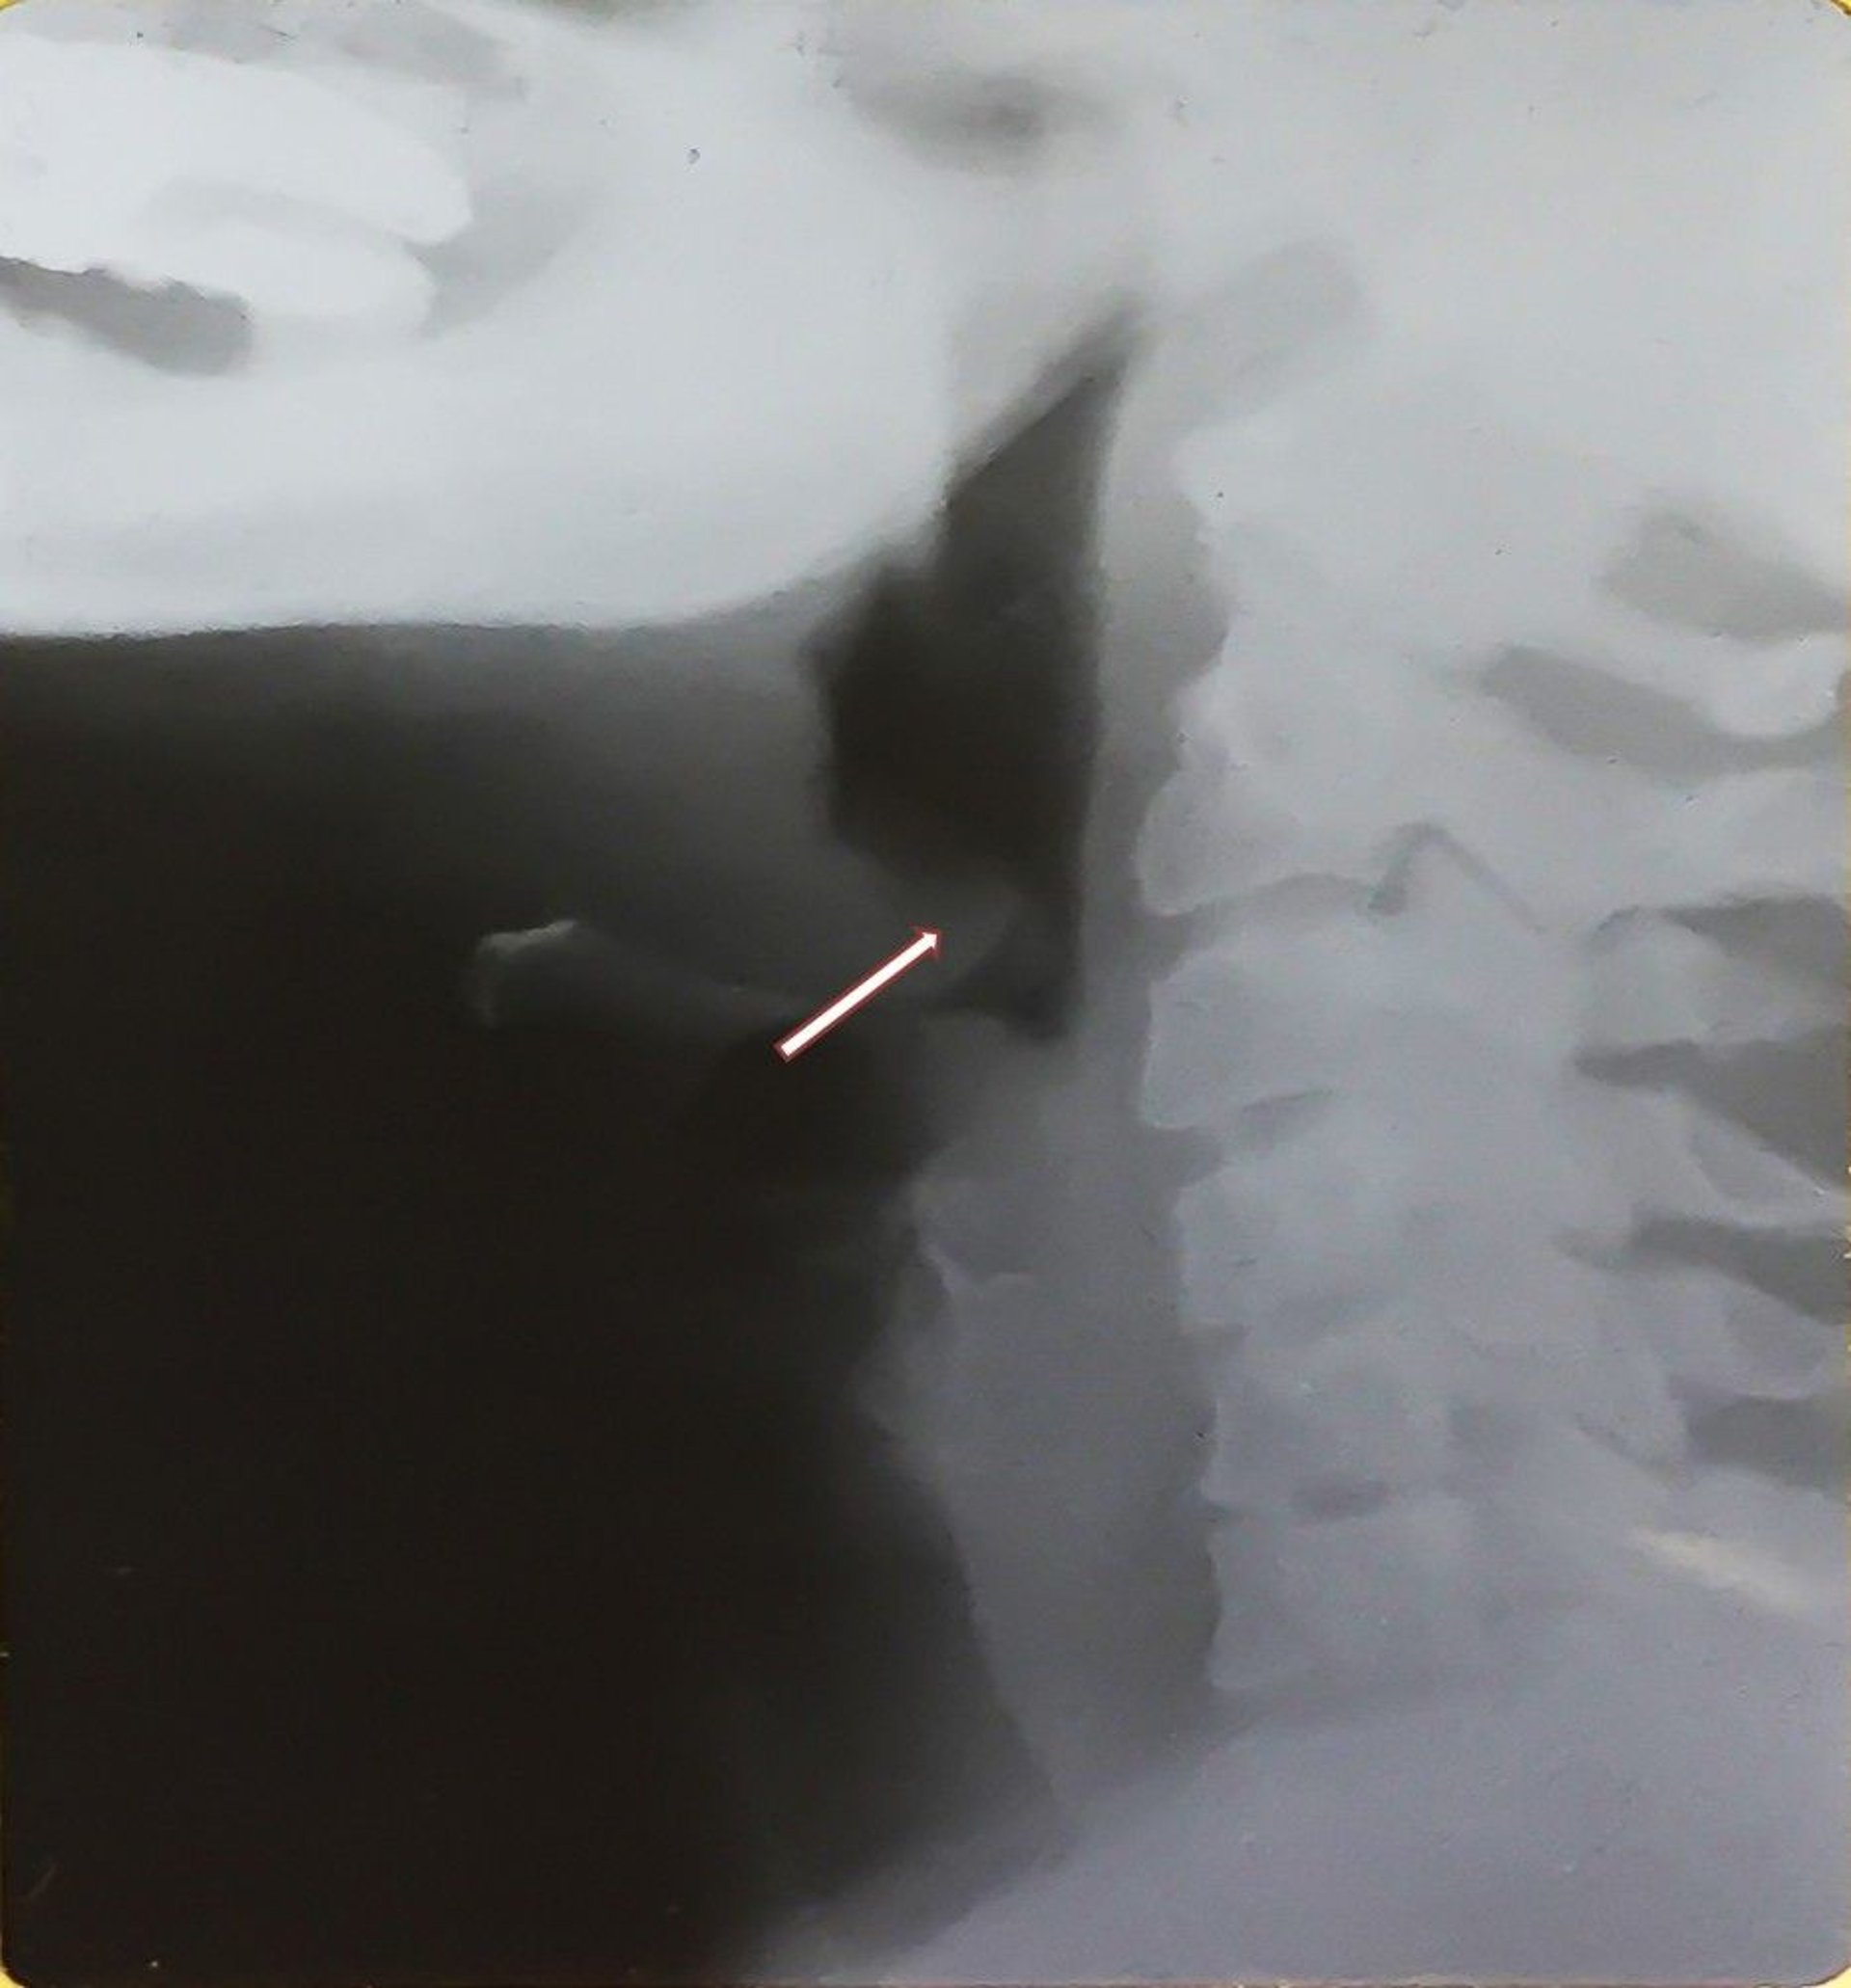

Epiglottitis (Erwachsener)

Diese Röntgenaufnahme zeigt eien vergrößerte Epiglottis (Daumenzeichen; siehe Pfeil), die für eine Epiglottitis und eine Ausdehnung des Hypopharynx charakteristisch ist. Beachten Sie die nach hinten verlagerte, verdickte Epiglottis.

Image provided by Clarence T. Sasaki, MD.